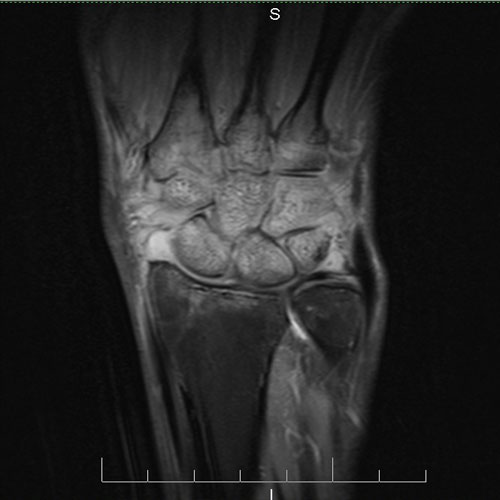

SCAN15

44 year old male with history of fall on outstretched hand. X ray of wrist joint showing Colle’s fracture.